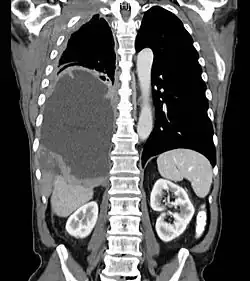

Mesothelioma Overview

Pathology

- Sarcomatous

- Epithelial (best prognosis of 3 subtypes)

- Mixed

- Pleural Involvement

Resectable disease

- Surgical resection possible in minority of patients

- Extrapleural pneumonectomy is surgical procedure of choice: Removes ipsilateral lung, parietal pleura, pericardium, diaphragm and mediastinal nodal dissection with reconstruction of the diaphragm.